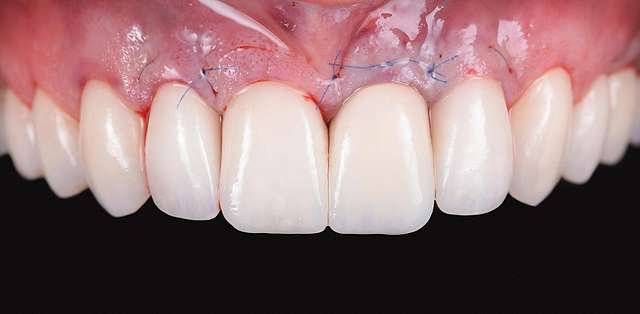

Grefa gingivala este o micro-chirurgie prin care se transplanteaza o mica bucata de tesut moale - gingie sau tesut conjuctiv (stratul intern al gingiei) pentru a acoperi un defect gingival. De obicei, acest tip de interventie este necesar pentru augmentarea implanturilor dentare, sau pentru a acoperi defecte cauzate de traume sau de afectiuni parodontale.Grefele se recolteaza din zona molarului de minte, sau de pe palat, si sunt transplantate in zona afectata.

Acesta interventie este una foarte delicata, lamele folosite pentru a efectua procedura sunt aceleasi folosite in oftalmologie, iar firele de sutura sunt si ele foarte fine. Firele se indeparteaza dupa 7-14 zile, in functie de caz, cand are loc vindecarea primara. Maturarea grefei dureaza aproximativ 90 zile, de aceea in momentul inserarii implanturilor preferam sa facem si grefa de tesut, pentru a sincroniza timpii de vindecare si ambelor proceduri.